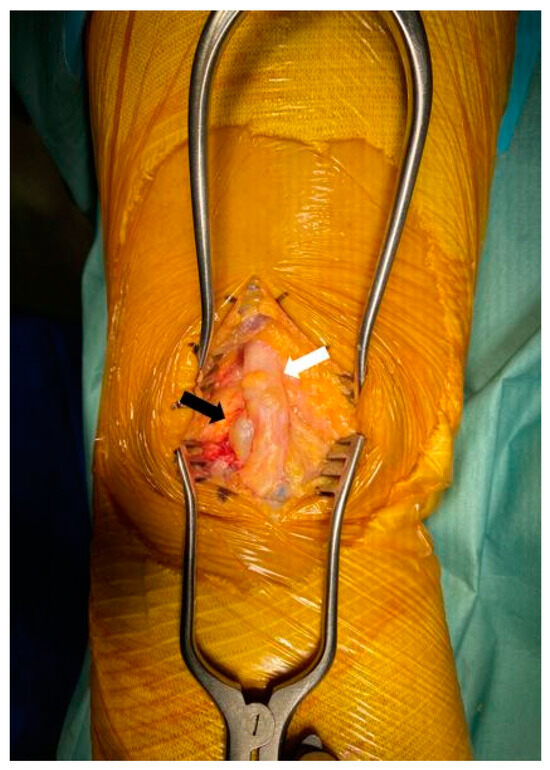

2.2. Surgical Procedure